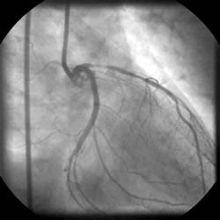

另外到現在為止最常用的X線冠狀動脈造影仍然是檢測冠狀動脈狹窄和堵塞的金標準。根據分析,冠狀動脈遍布規則,有一個突出的影子出來,反映是冠狀潰瘍,如果被口狀反映血栓性的血管的堵塞,間接提示板9塊某些病理改變特徵,但是本身並不能反映斑塊具體的成分。

這是冠狀動脈造影,動脈狹窄大家都熟悉了,這是中等度的狹窄,這是一個小的動脈流,這是在狹窄的基礎之上有缺損,這裡突出的影子,這就是所謂斑塊潰瘍,不僅要冠狀動脈軸樣硬化病變各種特種性病理改變的有關的症象。

這個病人是入院劇烈的胸痛,六個小時,插了管,血栓溶解掉了,堵塞的官腔開通了,但是在局部仍然有不規則的輕度的狹窄,大家知道所謂冠狀動脈血栓形成多半都是在由原有冠狀動脈狹窄病變基礎之上形成的,